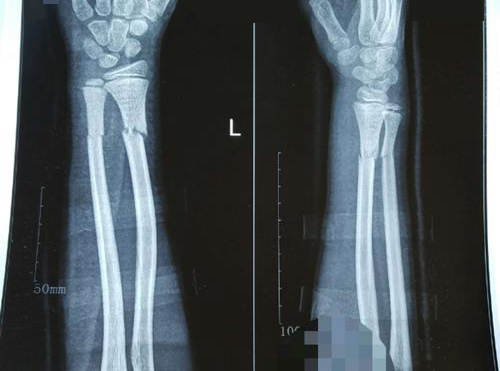

孙先生一天前由于不慎跌倒时手掌着地,当即感到手腕疼痛,几小时后出现局部肿胀、疼痛,手腕关节活动受限,遂来我院检查,发现关节有明显错位,诊断为上桡骨骨折。

与孙先生详细沟通后,建议行手术切开复位并固定,孙先生表示认同,并入住我院准备手术。